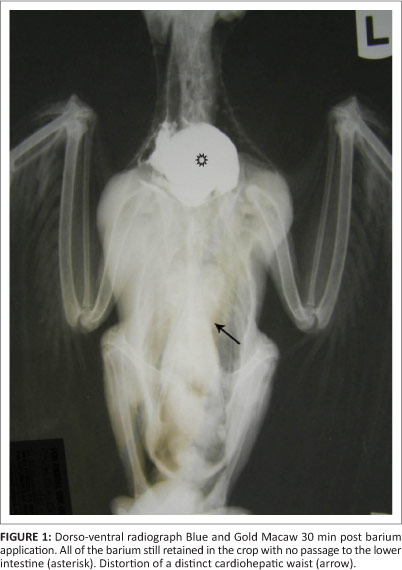

Bird 3, a 2-month-old blue and gold macaw from a different fancier, was examined in March 2011. This parrot had originated from the same breeding facility as birds 1 and 2. This particular bird presented with apparent ventricular obstruction. Radiographic studies revealed distortion of the shape of the cardiohepatic waist, and barium studies indicated very slow passage through to the ventriculus, with much of the barium remaining in the crop and eventually being regurgitated (Figures 1 and 2). A ventriculotomy was performed but no foreign object could be found. Despite supportive and antimicrobial therapy, the bird died two days later. A post-mortem examination was performed by the referring veterinarian and he described emaciation, haemorrhagic enteritis, nephrosis and pneumonia.